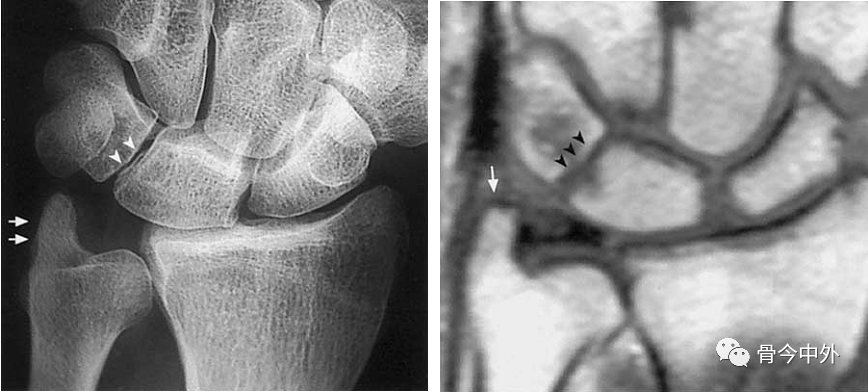

图6 尺骨茎突撞击综合症。男-44Y,慢性严重腕尺侧痛。尺骨茎突长约10mm(箭),月骨-三角骨间隙狭窄及退变(箭头)。